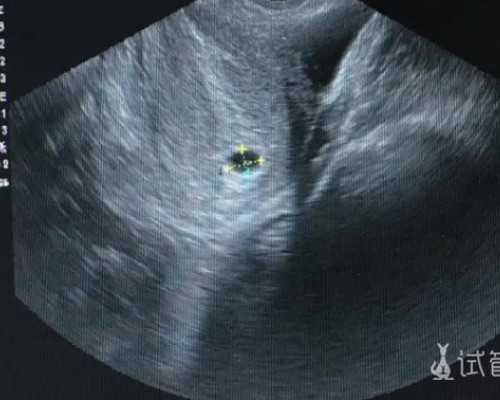

1. 最早:在B超确认孕满7周并且有胎心胎芽(胎芽≥10mm)时就可以进行检测,让准父母最早为宝宝做准备

1、B超确定怀孕满7周,胚芽长度达到10mm;